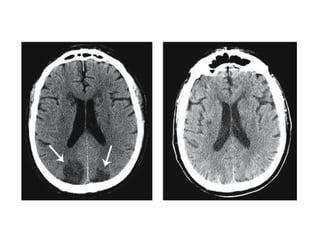

Large MCA infarct

1.Hypoattenuating brain tissue

• The diagnosis is infarction, because of the

location (vascular territory of the middle

cerebral artery (MCA) and because of the

involvement of gray and white matter,

which is also very typical for infarction.

2.Obscuration of the lentiform

nucleus

• Obscuration of the lentiform nucleus, also

called blurred basal ganglia, is an

important sign of infarction.

It is seen in middle cerebral artery

infarction and is one of the earliest and

most frequently seen signs.